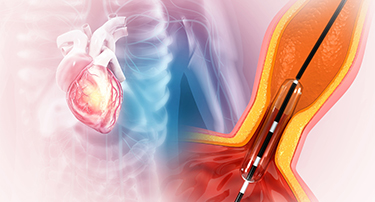

Carotid Artery Stenting vs Endarterectomy: Which Is Better for You

Stroke is a serious condition that happens when a blood clot or broken vessel prevents blood from reaching the brain. Due to this, one can experience paralysis, muscle weakness, slurred speech, and memory challenges, or even seizures.

Carotid Stenting: A Life-Saving Procedure to Prevent Stroke

You might face many instances in life where planning ahead could make all the difference. For example, if you want to crack a competitive exam, you analyze the past papers, concentrate most on the important topics, and then study hard to get the best outcome.

Is Cardiac Surgery Right for You?

It's not always necessary to have surgery for cardiac issues. Medication, lifestyle modifications, or nonsurgical procedures can sometimes be used to treat them. By using energy, for instance, catheter ablation can stop abnormal electrical signals from passing through your heart by creating tiny scars in the tissue surrounding it. Through a minimally invasive procedure called coronary angioplasty, a blocked or narrowed coronary artery is kept open by the insertion of a stent.